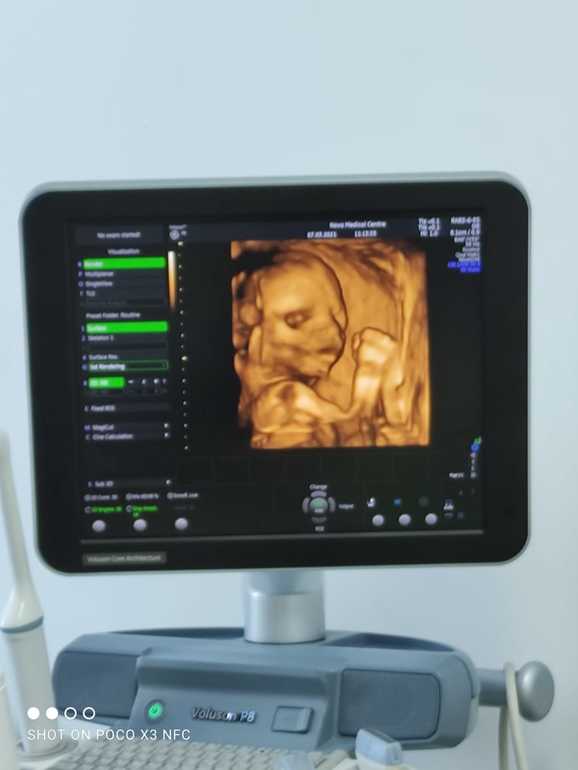

Анализы все в норме, 7 марта прошла 2 скрининг с малышом все отлично, пинается во всю, правда больше пинки начинаются ближе к ночи, папуля наш умиляется когда кладёт руку на животик потому что малышастик пинает 🙂🥰

И так наша эпопея с определением пола началась с 1 скрининга мы очень хотели узнать кто живёт у нас в домике, я в глубине души была настроена на доченьку т.к первый сыночек уже есть, муж со дня полосатого теста говорил что второй тоже будет сынок(🤣Ванга блин) и наконец-то нам окончательно и 100% сказали что у нас будет второй Мальчик ❤️🥰мы безумно рады (я конечно погрустила) , но потом муж сказал в третий раз точно пойдём за доченькой😂, а так буду наслаждаться мужским вниманием и если что внучек буду воспитывать😂 для себя сделала вывод что раньше второго скрининга не заморачиваться про пол🙂